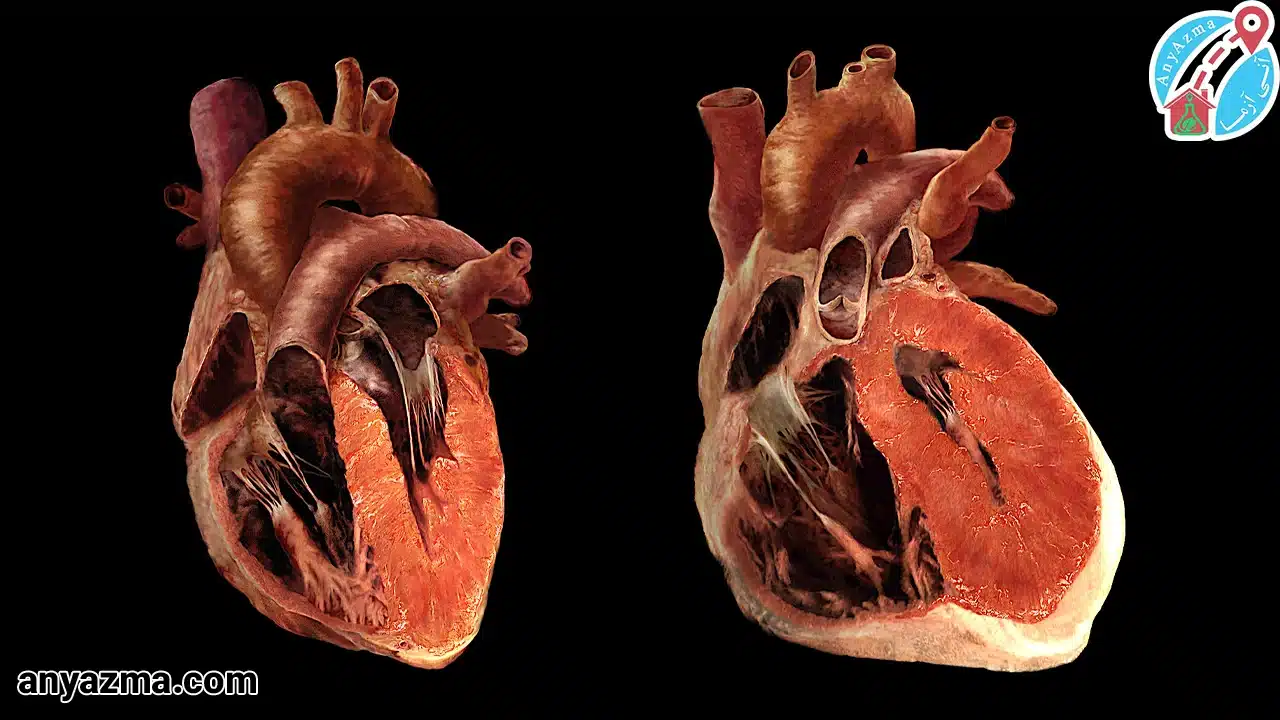

- کاردیومیوپاتی: این اصطلاح به گروهی از بیماریها اطلاق میشود که بر عضله قلب تأثیر میگذارند و آن را ضعیف، ضخیم یا سفت میکنند.

بزرگ شدن قلب یا کاردیومگالی، به خودی خود یک بیماری نیست، بلکه نشانهای از وجود یک مشکل زمینهای دیگر است که قلب را تحت فشار قرار داده است.